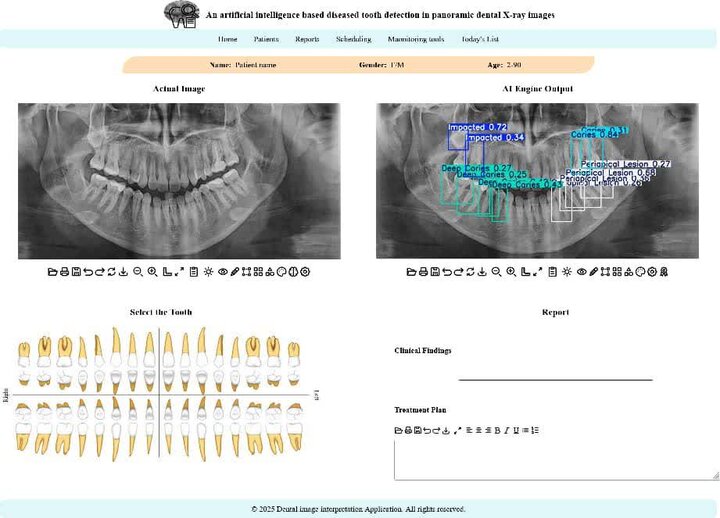

ظروفی یکی از نقاط قوت این پژوهش را کاربردی شدن پژوهش در قالب یک اپلیکیشن وب، عنوان کرد و گفت: یکی از نقاط قوت این پژوهش، کاربردی بودن آن است. این مدل در قالب یک اپلیکیشن تحت وب پیادهسازی شده تا دندانپزشکان و رادیولوژیستها بتوانند به سادگی از آن استفاده کنند. این سامانه با مشخص کردن محل دقیق مشکلات، به پزشک در اولویتبندی و تصمیمگیری سریعتر کمک میکند.

وی همچنین افزایش سرعت و اطمینان در تصمیمگیری بالینی را از دیگر مزیتهای استفاده از این سامانه در تشخیص مشکلات دندانپزشکی برشمرد و افزود: به گفته کارشناسان، بهرهگیری از چنین سامانههایی نه تنها سرعت فرآیند گزارشنویسی را افزایش میدهد، بلکه به عنوان یک ناظر دوم، میتواند با کاهش خطاهای ناشی از خستگی یا حجم بالای کار، دقت تشخیص نهایی را ارتقا دهد و نقش مکملی مؤثر برای متخصصان فک و صورت ایفا کند.